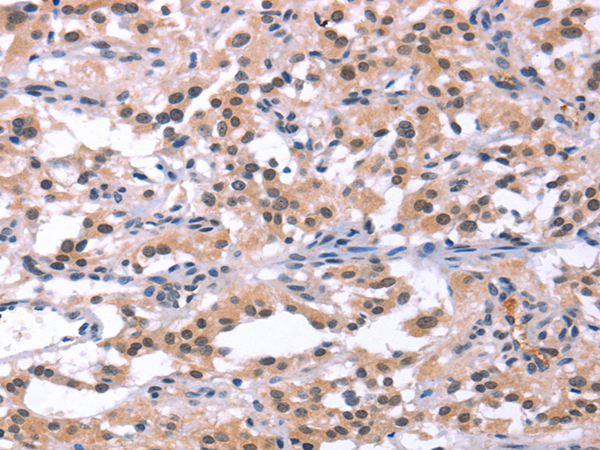

分类: 科研抗体货号: P04311别名: IMD9; TAM2; ORAT1; CRACM1; TMEM142A应用: WB,IHC反应种属: Human